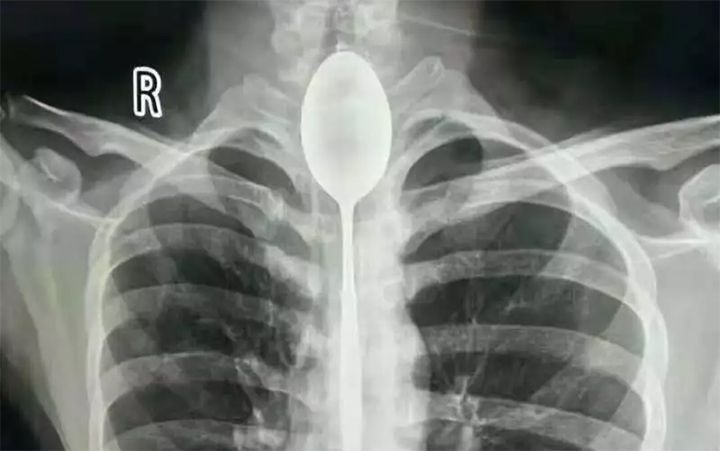

Desde su descubrimiento en 1895 por parte del profesor alemán Wilhelm Röntgen los rayos X han jugado un papel fundamental en las sociedades humanas. Son usados en campos tan distintos como el sanitario, la seguridad en el transporte e incluso la identificación de obras de arte. Su utilización está tan extendida que a veces deja imágenes tan curiosas como las recogidas en esta galería.